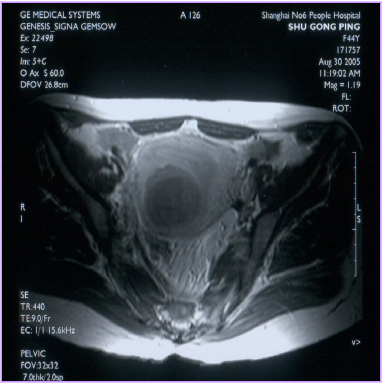

治療后壞死的子宮肌瘤不會消失,而是會發生纖維化,緩慢縮小,但對人體已經沒有危害了。最近,由于磁共振增強掃描(圖1,2)和超聲造影檢查技術(圖3,4)的應用,使治療效果的評價更加客觀和明確。

圖1 治療前MRI增強掃描